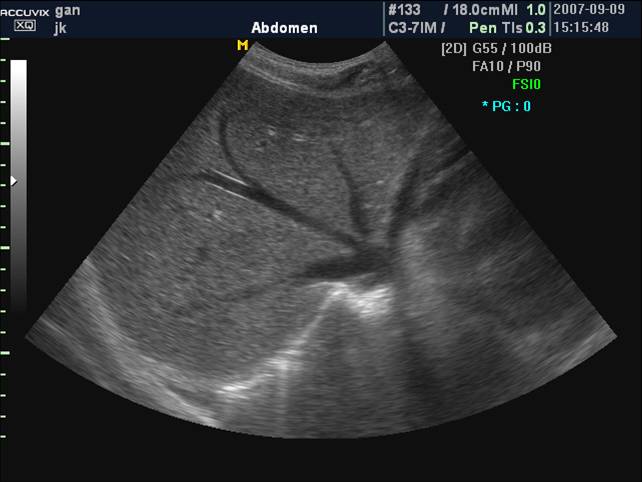

正常肝脏声像图:肝右肋缘下斜切